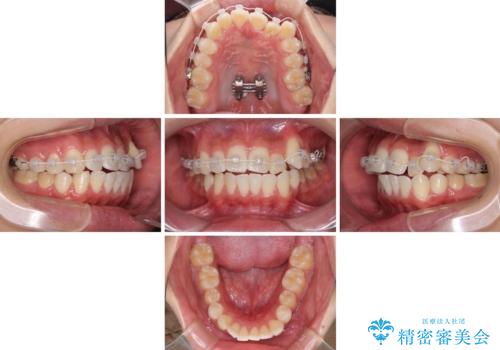

八重歯と奥歯のクロスバイト 上顎骨を拡大してインビザラインで矯正

上顎骨の幅が狭く、奥歯がクロスバイトとなっていたため、急速拡大装置を用いて上顎骨を側方拡大し、八重歯を収めるスペースを獲得しつつクロスバイトを改善することとしました。

上顎骨を思い通りに拡大できたため、当初の計画通りに非抜歯矯正で仕上げることができました。